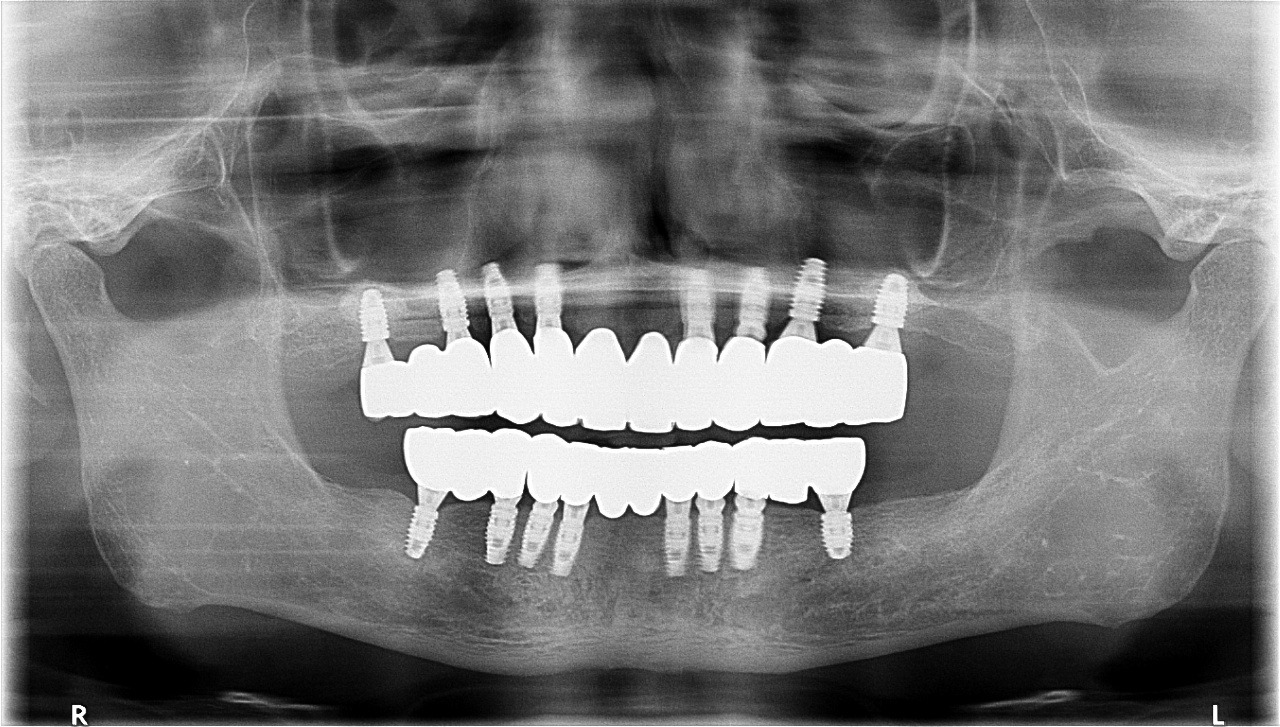

임플란트 브릿지는 치아를 연달아 여러 개 상실했거나 상악이나 하악 전체의 치아를 상실했을 때 주로 활용하게 됩니다. 최소한의 임플란트 픽스쳐(인공치근)를 식립하고, 임플란트의 머리인 크라운을 브릿지 형태로 제작해 씌우는 시술법인데요, 임플란트와 치아 브릿지가 결합된 형태의 인공치아입니다.

치아 브릿지는 여러 개의 치아를 다리모양처럼 이어 붙인 것을 말하는데요, 임플란트 브릿지는 임플란트 사이에 이러한 치아 브릿지가 놓여있는 형태이기 때문에 임플란트는 최소한으로 식립하면서 여러 개의 치아를 채운 것 같은 효과를 볼 수 있어 가성비가 뛰어난 치료로 꼽힙니다.

이렇게 임플란트 브릿지를 시술하면 임플란트 식립 개수를 줄일 수 있어 비용이 절감되고, 치조골에 가해지는 부담도 줄어들어 임플란트와 브릿지의 장점을 모두 누릴 수 있습니다. 거기다, 환자의 구강 상태에 맞춰 가장 합리적인 수의 임플란트를 식립하기 때문에 흔들리거나 탈락하는 등의 부작용도 거의 발생하지 않지요.